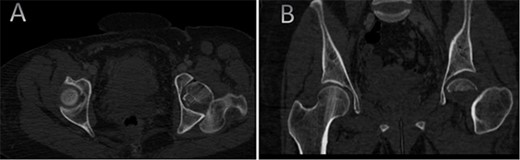

A medically free 42-year female presented to our institute as a life-saving case from a different hospital as she was a victim of unrestrained road traffic accident 2 days prior to presentation. Upon assessment in the emergency department (ER), she was conscious and oriented, and was found to have bilateral lung contusion, and multiple fractures of ribs. She also had a left sided vertical femoral head fracture dislocation comprising around 40% of the femoral head (Fig. 1). Closed reduction under conscious sedation was done in the ER, which was successful based on post-reduction imaging studies (Fig. 2). Her chest injuries were treated with chest tube and observation for 10 days. During that time, discussion was made with the patient regarding her situation and conservative management was chosen by way of bed rest and continuation of skeletal traction for 4 weeks with serial radiographs in the hospital on a weekly basis after clearance of her chest injuries. Skeletal traction was discontinued and she was advised to continue bed to wheelchair mobilization for an additional 2 weeks. After 6-weeks from the injury, a Computed Tomography (CT) was done to the patient and revealed signs of fracture healing (Fig. 3). At 3-years after the injury, she was found to have full painless range of motion of the affected hip and has resumed her activity of daily living without any complaints and the images showed a symmetrical joint space of the hips (Fig. 4).

CT scan of the chest, abdomen, and pelvis showing axial (A) and coronal (B) cuts of a left sided Pipkin I fracture comprising large surface of the femoral head with posterior hip dislocation.